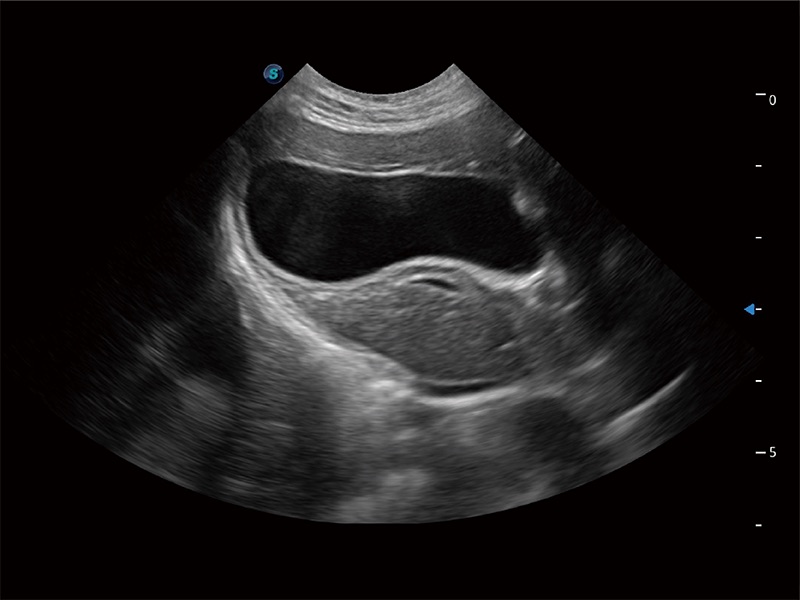

高性能和先进的临床应用工具可以为动物医生提供临床信心。ProPet 80 搭载了先进的腹部和浅表应用工具,帮助医生在日常临床实践中发挥前所未有的作用。

极大提升超低速微细血流的检出能力,同时更精准地滤除软组织和超声信号,为兽用医生提供以往无法通过常规血流获得的疾病诊断信息。

在传统二维血流成像的基础上,呈现血流的立体感,具有动感的生命力之美。即便是微小的血管也能轻松应对,提高了血流的视觉敏感性。

操作简便,无需高频度外力作用即可真实反映组织的形变,快速评估肿瘤良恶性。

非线性融合造影成像充分利用谐波和基波信号,为难以观察的血流进行增强显像。可用于线阵、凸阵、微凸阵、相控阵探头。